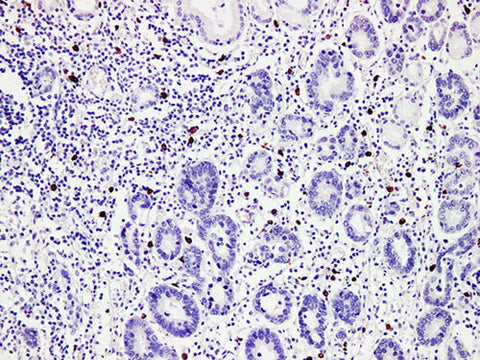

Applications IHC-P

Tissue Specificity Renal cancer

Mast cell tryptase(MCT) is widely expressed in respiratory tract, gastrointestinal tract, skin and other tissues. It is mainly used in the study of respiratory system, gastrointestinal system diseases and their tumors.